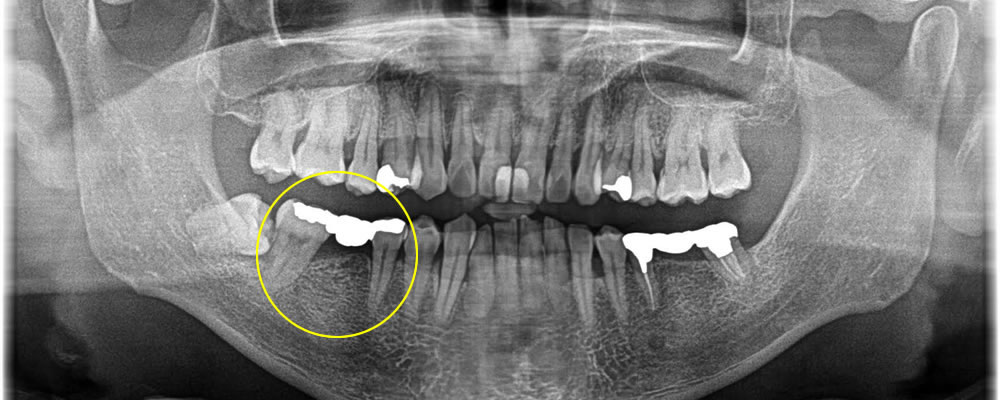

ブリッジ部分をインプラントで治療した症例

こちらの患者さまは、昔治療を行ったブリッジをインプラントにしていきたいとの事でご来院いただきました。

まずブリッジを除去し、フィクスチャーの埋入を行いました。この際、切開範囲を最小限に抑えて術後の痛み、腫れの出にくい方法でインプラントオペを行いました。